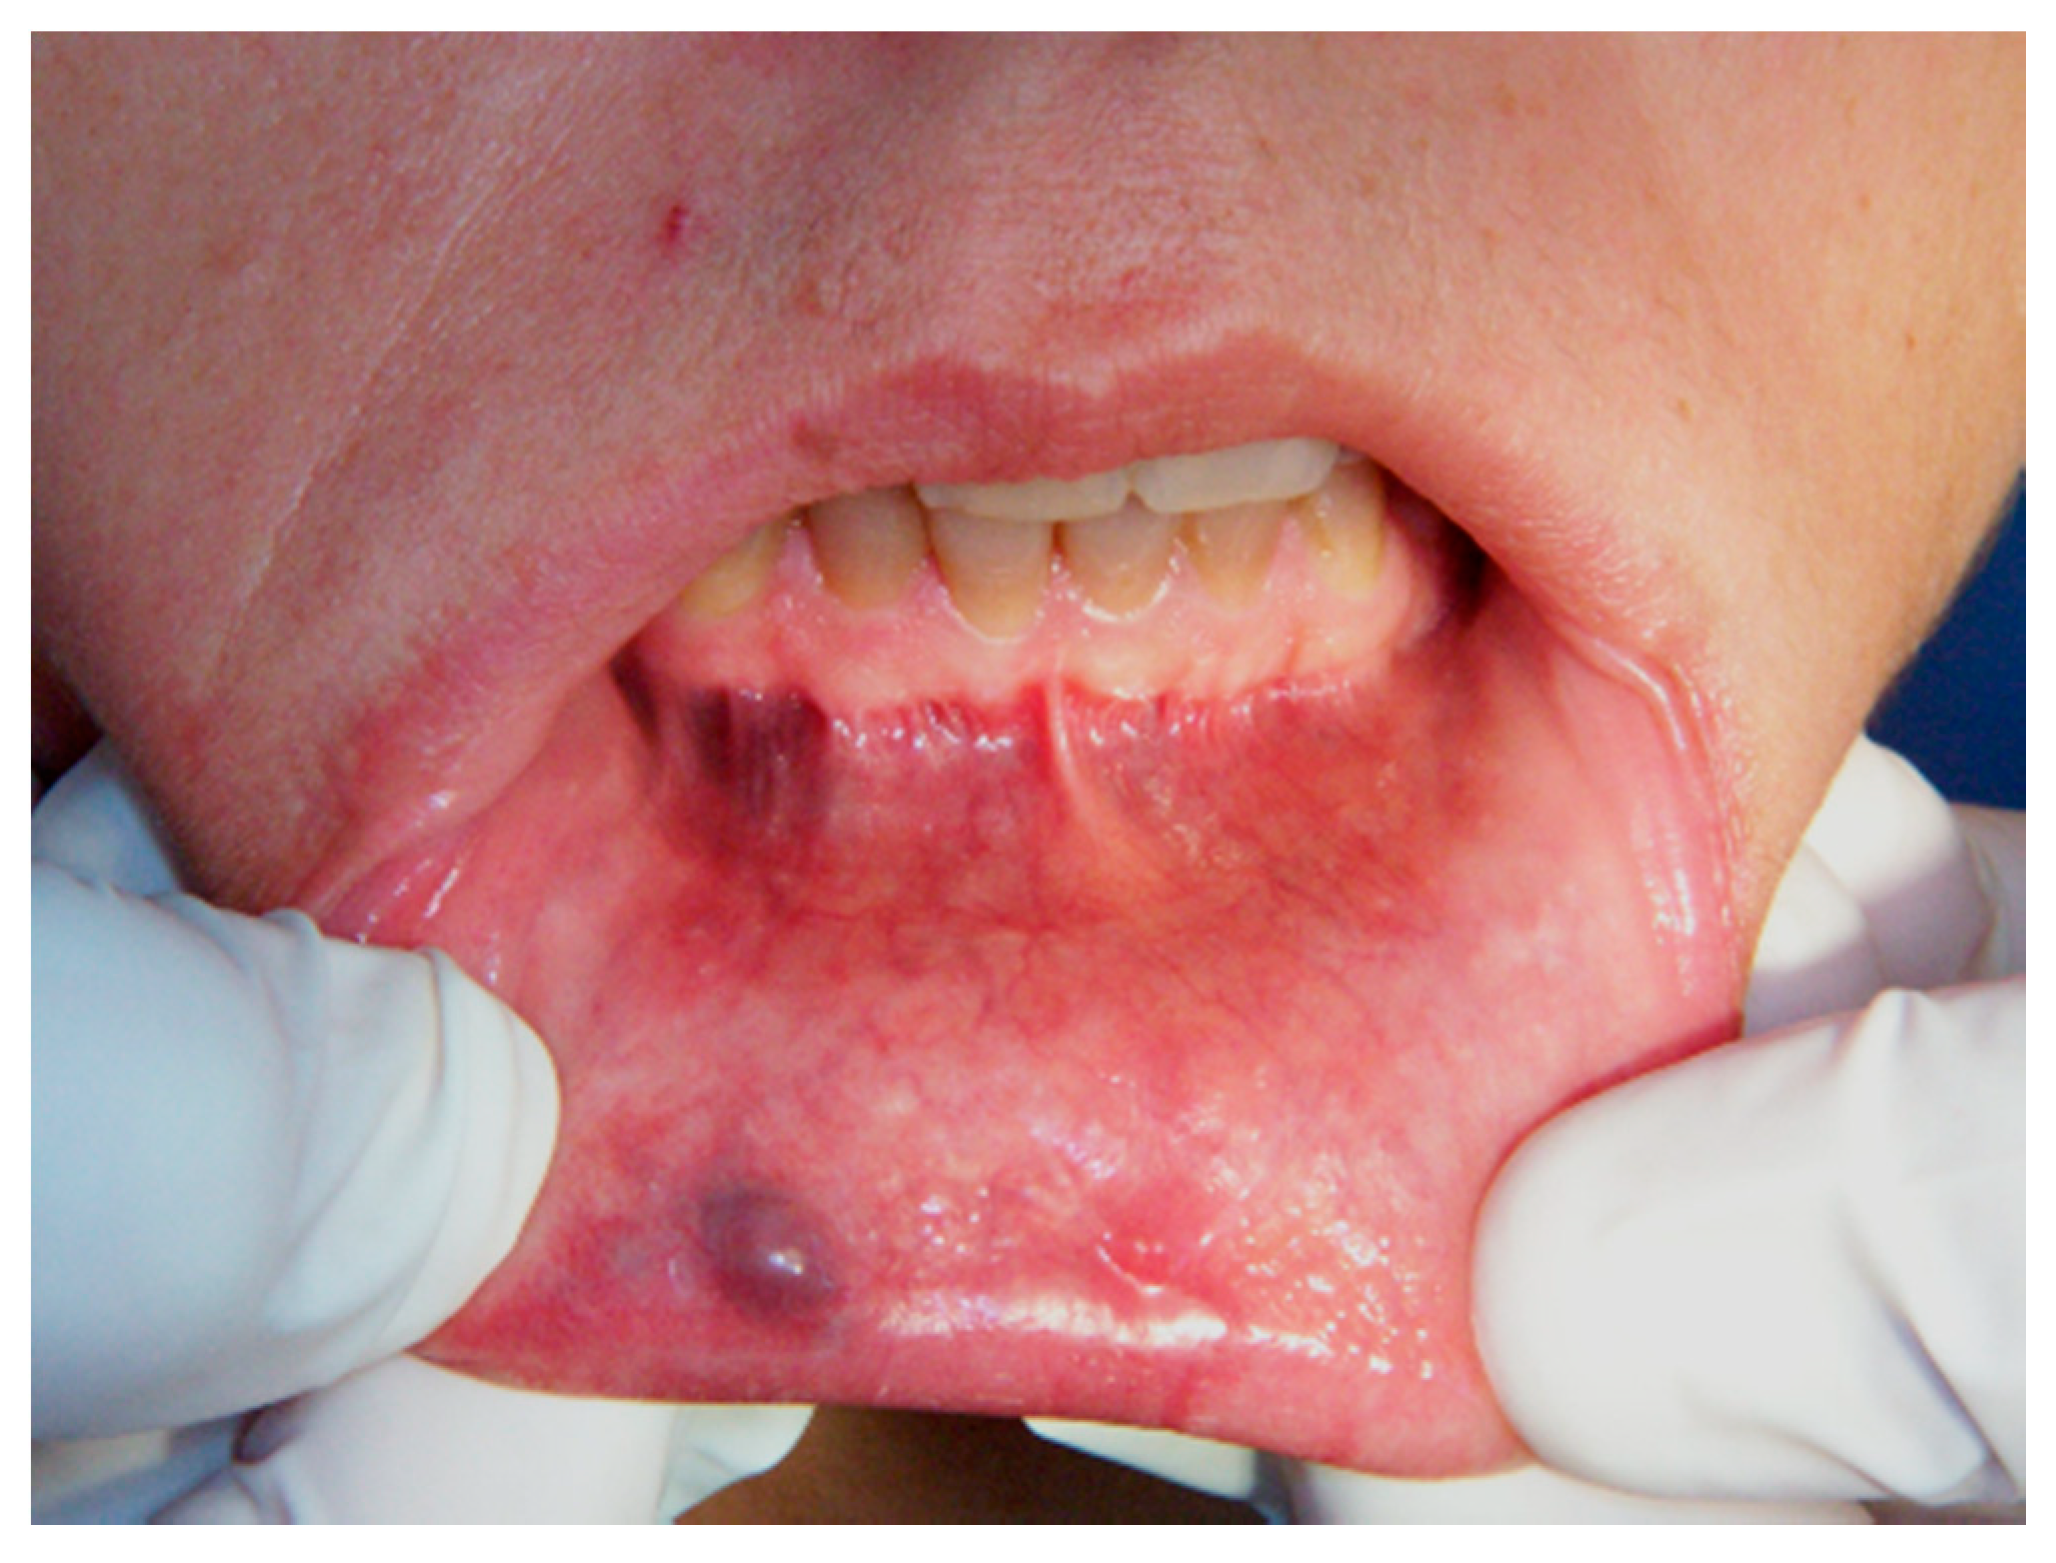

Figure 1.

Clinical aspect of venous malformation (VM) on the lower lip.